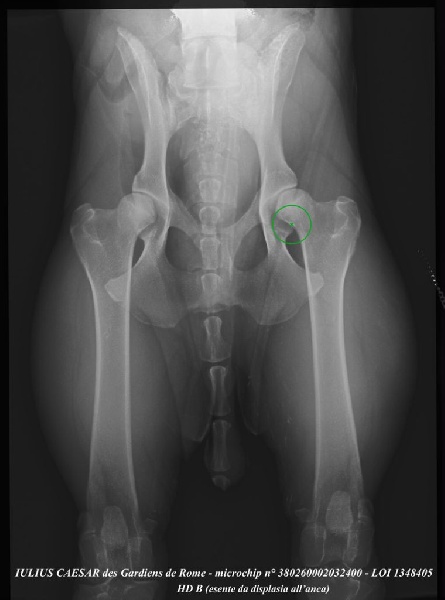

| Puce | 380260002032400 |

| N° origine | LOI 1348405 |